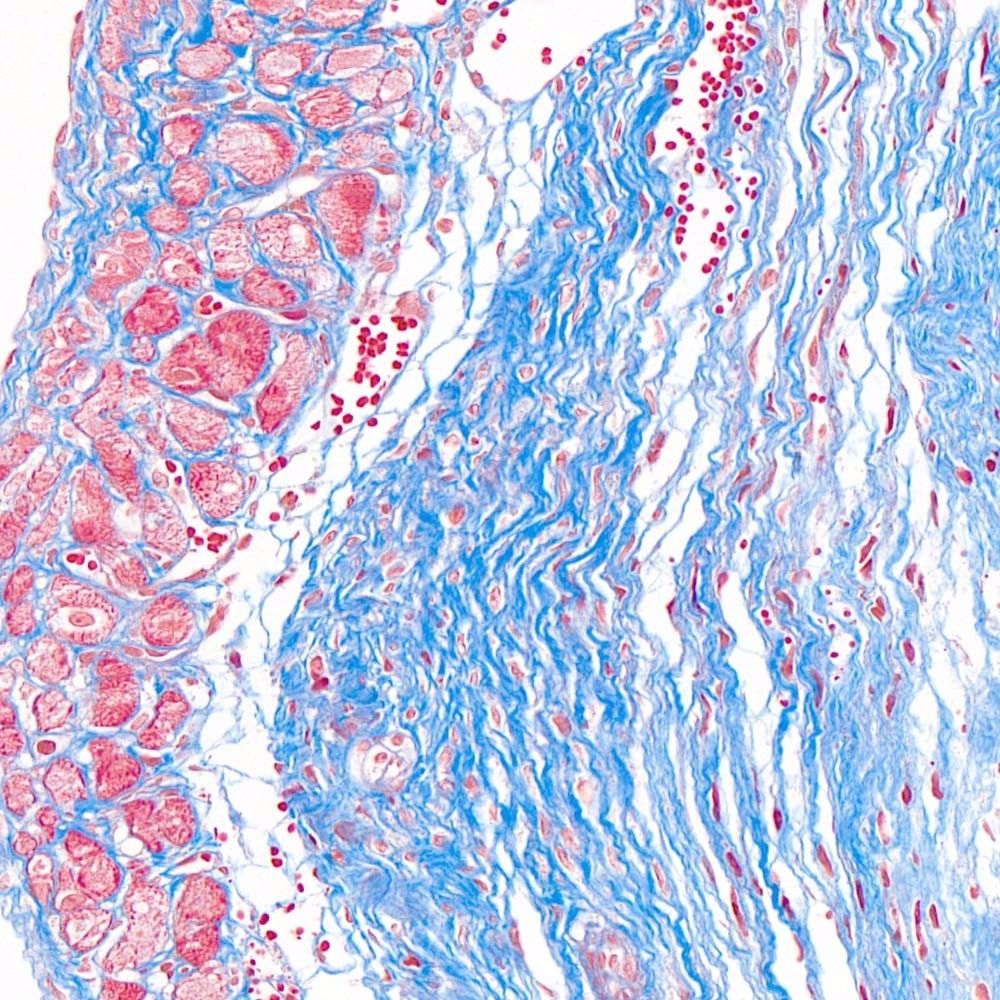

首先,讓我們深入探討MASSON染色的原理。MASSON染色的原理與陰離子染料分子的大小和組織的滲透性密切相關。染料的分子量決定了其穿透組織的能力:小分子量的染料更容易穿透結構致密、滲透性較低的組織,而大分子量的染料則更傾向于進入結構疏松、滲透性較高的組織。在MASSON染色中,由于肌纖維間隙較小,而膠原纖維間隙較大,因此小分子量的麗春紅染料更容易滲透進入肌纖維并使其呈現(xiàn)紅色,而大分子量的苯胺藍染料則主要進入膠原纖維并使其呈現(xiàn)藍色或綠色。

MASSON染色的陽性意義在于,它能夠幫助研究人員區(qū)分膠原纖維和肌纖維,從而觀察病變組織中纖維結締組織的增生和分布。當MASSON染色結果呈現(xiàn)陽性時,通常意味著局部組織中存在膠原纖維的增生。這種增生可能是由于局部皮膚出現(xiàn)炎癥或組織增生等病理 過程所導致的。因此,MASSON染色的陽性結果可以作為判斷組織纖維化程度的一個重要指標。